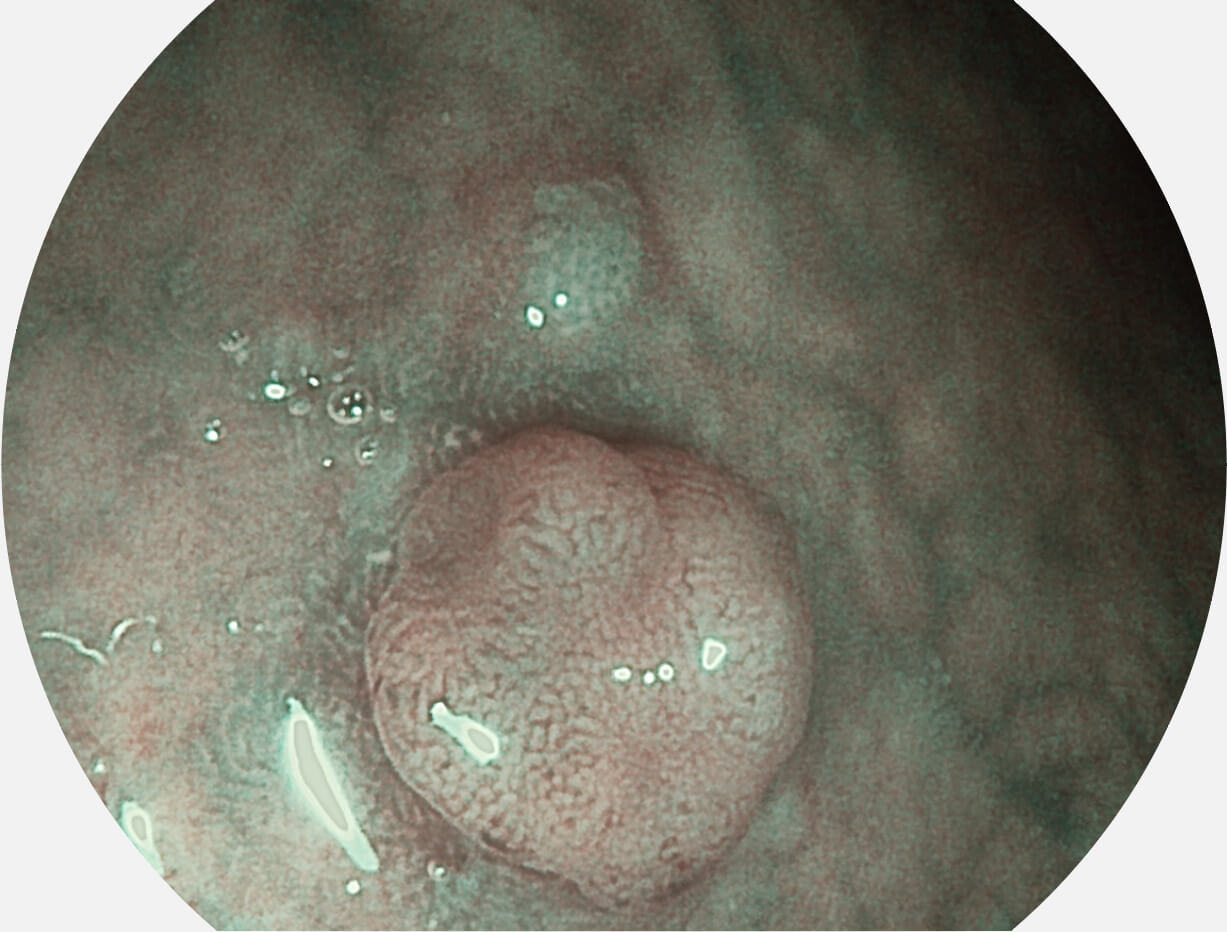

白光图像

VIST图像